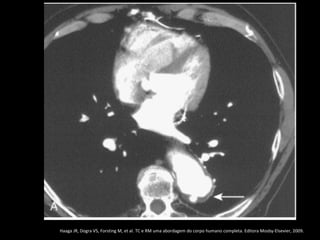

Ruptura: extravazamento do contraste e hemotórax

Haaga JR, Dogra VS, Forsting M, et al. TC e RM uma abordagem do corpo humano completa. Editora Mosby-Elsevier,

2009.

Complicações do aneurisma aórtico

O sinal do crescente hiperdenso na parede da aorta

representa hematoma agudo com sangue contido

no interior do trombo do aneurisma;

Diagnosticado melhor na fase sem contraste;

Ruptura da aorta: infiltração da gordura

mediastinal, hemomediastino, hemopericárdio ou

hemotórax;